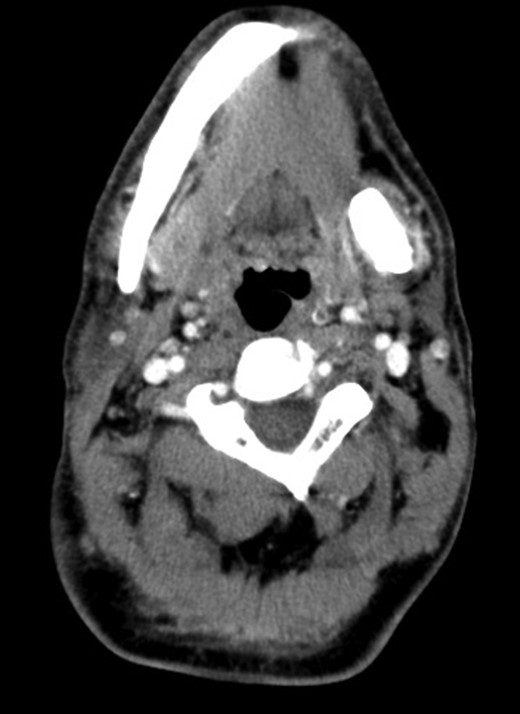

A 42-year-old male patient was admitted to our department with the complaints of recurrent pain, swelling and redness in the left submandibular area for 6 months. Swelling and hyperemia on the left submandibular region was observed. Intraoral bimanual palpation revealed a hard and tender mass, ∼6 × 5 cm in size. The orifice of Wharton duct was hyperemic and swollen, and the floor of the mouth was elevated in the left. A preliminary diagnosis of submandibular sialolithiasis was made and computerized tomography (CT) scan was performed. In the CT imaging, a calcified mass of 42 × 17 mm size in the left submandibular gland was detected (Fig. 1). Oral antibiotics and non-steroid anti-inflammatory drugs for 2 weeks were prescribed to treat the acute inflammation of the gland and a follow-up visit was planned. Two weeks later, it was seen that the acute inflammation of the gland had subsided and resection of submandibular gland was planned with the informed consent of the patient. Submandibular gland resection was performed. Intraoperatively, it was found that the body of the gland was totally filled with a giant sialolith and the gland parenchyma was atrophic (Fig. 2). Pathologic examination confirmed the diagnosis of chronic sialadenitis and a giant sialolith of 35 × 25 × 15 mm in size. The postoperative period was uneventful and the patient recovered without any complication.

Coronal CT image showing the calcified mass of 42 × 17 mm in the left submandibular gland.